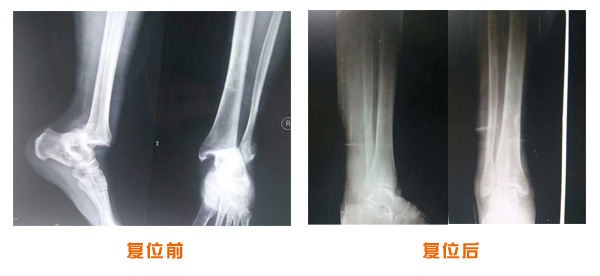

肥城市安駕莊梁氏骨科醫(yī)院是一所以梁氏手法正骨配合膏藥為特色的現(xiàn)代化??漆t(yī)院。

梁氏骨科術(shù)始創(chuàng)于清雍正年間,歷經(jīng)八代,至今已有三百年歷史。據(jù)1929年泰安縣志載“梁瑞圖先生,字增生,號蓮峰,安駕莊人,精岐黃并發(fā)明接骨,凡跌打車凡跌打車軋皮不破而碎骨者......【詳細】 |